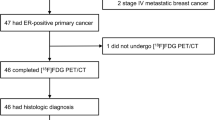

Patient Characteristics

Nineteen women were enrolled in this study between November 2008 and January 2011 and underwent FES-PET imaging. Patient characteristics and outcomes are summarized in Table 1. Five patients had de novo stage IV disease, and the 14 others were newly diagnosed as stage IV after having an ER+ primary breast cancer 3 months to 29 years earlier. Fifteen patients successfully underwent biopsy of metastases. In patients with recurrent disease 3/11 (27 %) had ER- biopsy results. In four patients with de novo metastatic disease, available primary and metastatic site biopsies concordantly expressed ER.